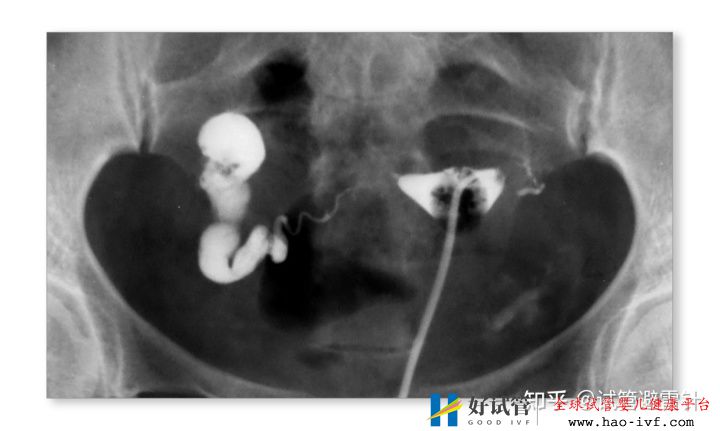

按照不同授精部位,如阴道、宫颈管、(QQ:914935817)宫腔、输卵管和腹腔的授精,分别称为阴道内人工授精(IVI)、宫颈管内人工授精(ICI)、宫腔内人工授精(IUI)和输卵管内人工授精(IFI)。